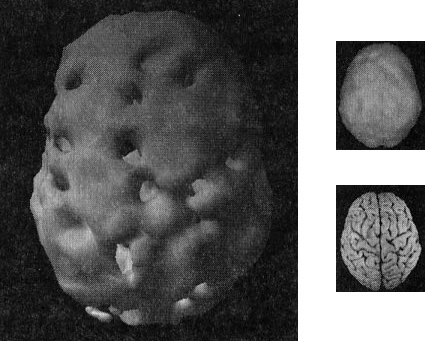

Наконец, рис. Г показывает трехмерную картину активности здорового мозга, вид снизу, а под ней находится иконка с моделью мозга в той же проекции. ![]() Помните, что трехмерные поверхностные сканы помогают увидеть малоактивные области, а трехмерные функциональные сканы помогают обнаружить гиперактивные области. Как не бывает двух одинаковых лиц, так нельзя встретить и два одинаково выглядящих мозга. С эстетической точки зрения бывают красивые и уродливые, банальные и причудливые мозги. Но всегда справедливо — и это доказали 30 000 проведенных мною сканирований, — что активность здорового мозга должна быть достаточной, полной, равномерной и симметричной. В здоровом мозге целы все важные участки, и все они работают гармонично. Возрастные вариации нормальны. Сканы мозга детей и подростков показывают большую активность, чем у взрослых. Но даже у пожилых людей мозг будет здоровым, если о нем заботились в течение жизни. Давайте взглянем на несколько примеров здорового и не очень здорового мозга. Однажды я предложил студентам стать добровольцами в исследовании функционирования мозга. Кристи, одна из вызвавшихся, воскликнула: «Вам обязательно нужно проверить мою бабушку Анну. Ей 82 года, но среди всех, кого я знаю, она одна из самых нормальных. Она вам понравится!» Бабушка согласилась, и мы провели томографию. Действительно, обнаружилось, что мозг этой пожилой женщины здоров, а ее жизнь соответствует всем критериям профилактики здоровья мозга (она не употребляла наркотики, не получала травм головы, не имела родственников первой степени с психиатрическими заболеваниями и т. д.). В течение 58 лет Анна была замужем, всегда оставаясь любящей женой, матерью и бабушкой, ее ум был острым и деятельным. Кроме того, она активно участвовала в делах местной церкви и муниципалитета. Она создала прочные и длительные отношения с родными и друзьями. Скан мозга Анны — один из самых здоровых в моей базе данных (рис. 2.5 и 2.6). Скан здорового мозга Анны, 82 года Рис. 2.5 Вид сверху Полная симметричная активность ![]() Рис. 2.6 Вид снизу Полная симметричная активность ![]() Двадцатилетний Брюс, несмотря на молодость, годами злоупотреблял наркотиками: героином, марихуаной, амфетаминами, галлюциногенами, экстази и обезболивающими. Я познакомился с ним, когда снимал образовательный фильм о вреде наркотиков. Брюс не был способен завязать со своим пристрастием. Отношения с родными разладились. Он стыдился себя и своего поведения. Как вы сами можете увидеть, мозг 82-летней Анны на томограмме выглядит значительно здоровее поврежденного наркотиками мозга молодого Брюса (рис. 2.7). Поврежденный наркотиками мозг Брюса Рис. 2.7 Вид сверху Значительные повреждения ![]() В норме с возрастом мозг становится все менее активным, поэтому если очень пожилая женщина обладает значительно более здоровым мозгом, чем 20-летний парень, значит, у этого парня серьезные неприятности. Я убедился, что люди со здоровым мозгом ведут себя эффективно и всегда движутся к поставленным целям. Они прекрасные сотрудники, супруги, родители, друзья и граждане. Люди же с поврежденным мозгом с трудом бредут по жизни. Вспомните про болезнь Альцгеймера (БА): можно ли сказать, что заболевшие ею способны полноценно проявлять свою волю и личность? Вероятно, нет. У людей с БА функционал мозга значительно поврежден. От этой болезни страдала мать моей подруги Айзы Гиббонс, основавшей ряд центров поддержки для людей с БА и членов их семей. Мать Лизы из доброй, мягкой женщины превратилась в озлобленного, иррационального и агрессивного человека (рис. 2.8). Мозг пациента с болезнью Альцгеймера Рис. 2.8 Вид сверху Значительно снижена активность в задних частях мозга ![]() Гиперактивность мозга часто связана с обсессивно-компульсивным [2] и биполярным расстройствами и другими заболеваниями. 17-летняя Хитер очень много пила и не ладила с семьей. Я сделал томографию мозга ей и ее брату для телепередачи «Правда о выпивке», которая позже получила премию «Эмми». На сканах вы видите области очень высокой активности (рис. 2.9). Неудивительно, что девушка начала пить — она пыталась успокоить свой мозг. Гиперактивный мозг Хитер Рис. 2.9 Вид функциональной активности снизу Значительно снижена общая активность ![]() 45-летний Джимми обратился ко мне с посттравматическим стрессовым расстройством, вызванным пожаром. Томограмма показала множественные области повышенной активности, о которых можно было догадаться, судя по его тревожности, депрессии и страхам. Эмоциональные центры его мозга работали чересчур напряженно, и моей задачей было их успокоить (рис. 2.10). Гиперактивный мозг Джимми Рис. 2.10 Вид функциональной активности снизу Повышенная активность в глубоких областях мозга ![]() А теперь вернемся к разнице между «волевым» и «мозговым поведением». Плохо работающий мозг лишает людей силы воли и провоцирует деструктивные поступки. Люди с обсессивно-компульсивным расстройством (ОКР), синдромом Туретта (СТ) или зависимостью от наркотиков, скорее всего, стали жертвами своего мозга. Для ОКР характерны вызывающие огорчение навязчивые мысли или компульсивное поведение (непрерывная проверка дверных замков, постоянное мытье рук, следование ритуалам). Даже если человек понимает, что его мысли и поступки иррациональны, он все равно не может от них отказаться. В тяжелых случаях такие мысли и действия занимают большую часть дня. Сканы показывают, что при ОКР гиперактивна передняя часть мозга, провоцирующая навязчивые мысли (обсессия) или действия (компульсия). |